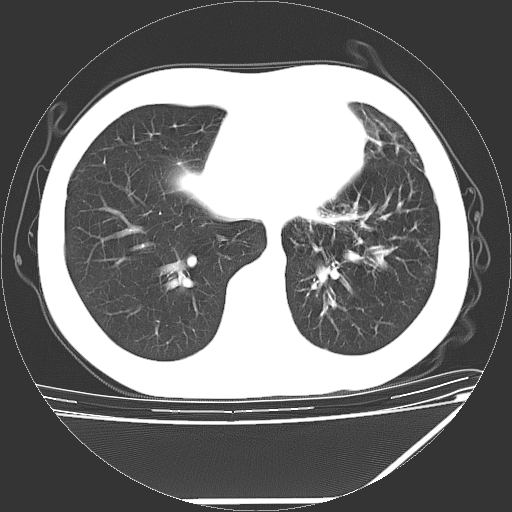

男,13岁,咳嗽、咳痰伴发热一周。

中上纵隔见多枚淋巴结肿大,部分相互融合成团片,左肺门增大,上叶支气管变窄,肺内多处斑片状 索条状及棉絮状致密影。临床“男,13岁,咳嗽、咳痰伴发热一周。”首先考虑:原发综合征!不除外淋巴瘤可能!

纵隔多发肿大淋巴结,部份有融合改变。双肺血管气管束增厚,以肺门为中心向外周散发,以左肺下叶为明显。考虑淋巴瘤可能性大。不除外原发综合征。

中上纵隔见多枚淋巴结肿大,部分相互融合成团片,左肺门增大,上叶支气管变窄,左肺支气管血管束增粗,可见磨玻璃样影。临床“男,13岁,咳嗽、咳痰伴发热一周。”首先考虑:淋巴瘤可能性大!

中上纵隔见多枚淋巴结肿大,部分相互融合成团片,纵隔内脂肪间隙模糊,左肺门增大,上叶支气管变窄,左肺支气管血管束增粗,可见磨玻璃样影。考虑纵隔淋巴管炎